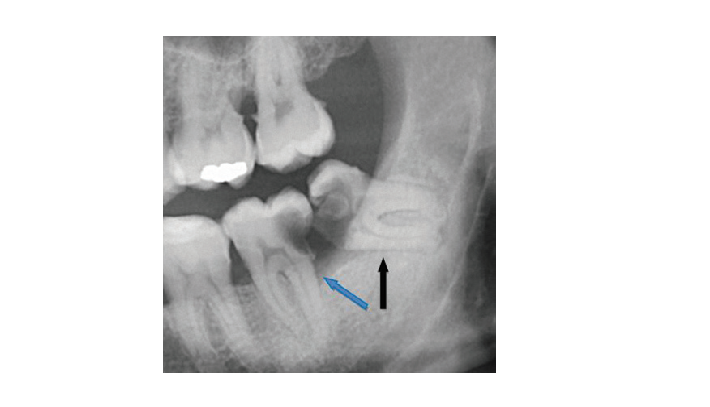

בתמונה: שן בינה שאובחנה אך לא נעקרה וכתוצאה מכך נגרם אובדן של שורש השן הסמוכה